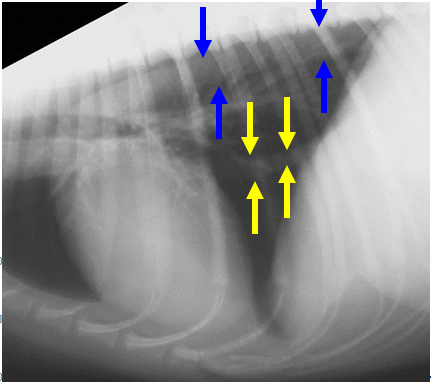

What can be seen here?

Caudal mediastinum

Blue – aorta

Yellow – vena cava

Don’t normally see normal oesophagus on radiograph